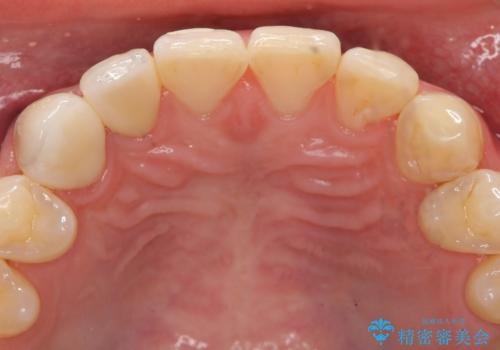

- 右上2、3番目の歯の色・形が気になるといらっしゃった方の症例です。

古い樹脂を除去後、オールセラミッククラウンによる補綴を行いました。